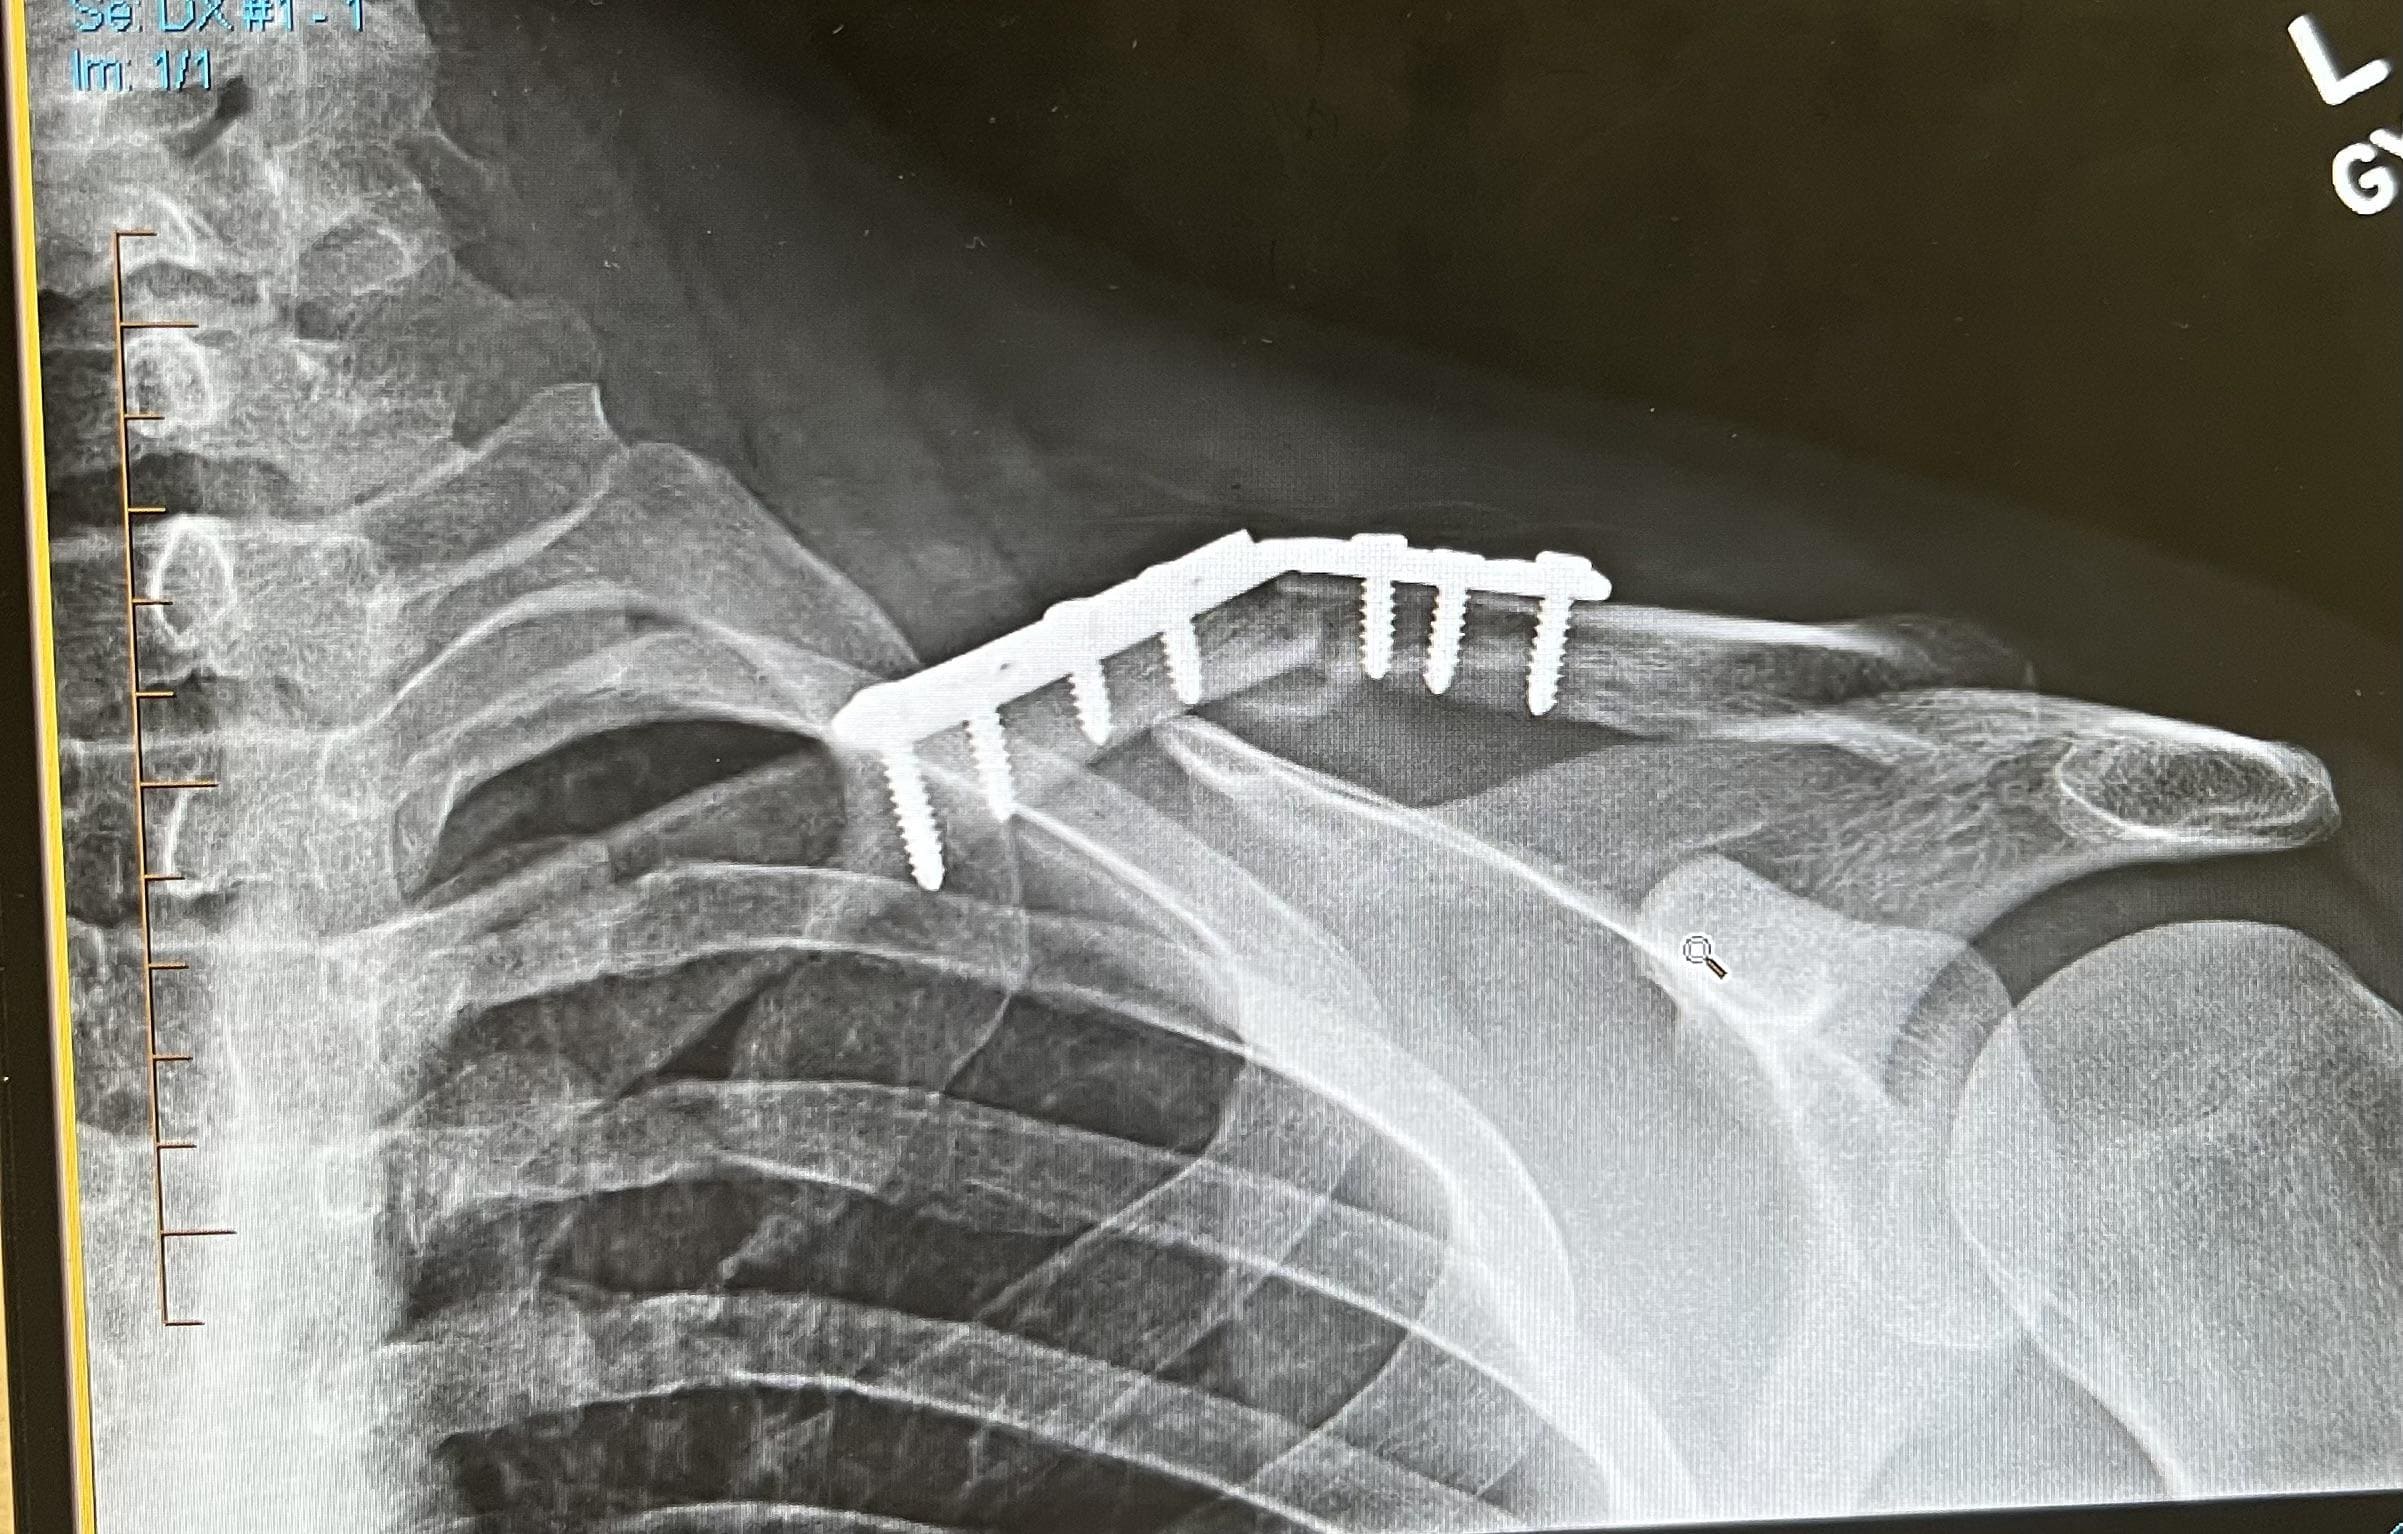

Just when I was starting to trust that knee again, I snapped my collarbone. Skateboarding.

It had been almost a year since I’d really ridden. My body felt alien… like it wasn’t mine anymore. My knee had been rebuilt, the collarbone still ached when I reached across my body and all I could think about was how fragile it all felt.

The real gut punch was the knee. Torn meniscus and ACL. Surgical repair. Months of hobbling around, then limping, then endless physio where bending my leg to ninety degrees felt like climbing Everest. I hated it. Every squat and stretch felt like it wasn’t about getting stronger — it was about trying to claw my way back to “normal.”